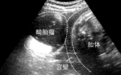

赵女士的故事,是许多畸胎瘤患者共同心声的缩影。当她因腰痛而踏上求医之路,却意外得知卵巢深处藏着一个“异样的世界”——畸胎瘤,内含毛发、牙齿乃至骨骼,这种突如其来的冲击,无疑是对心理与身体的双重考验。

泰安志康互联网中医院的妇科专家指出,畸胎瘤虽为卵巢生殖细胞肿瘤的一种,但其复杂性与多样性要求治疗方案的精准与全面。在充分评估赵女士的病情后,医院采用了中医辨证施治的方法,结合患者体质与病情特点,制定了针对性的中药治疗方案,旨在调和气血、活血化瘀、软坚散结,从根本上改善机体环境,促进瘤体缩小乃至消失。同时,对患者的健康数据进行实时监测与分析,为精准医疗提供了有力支持。